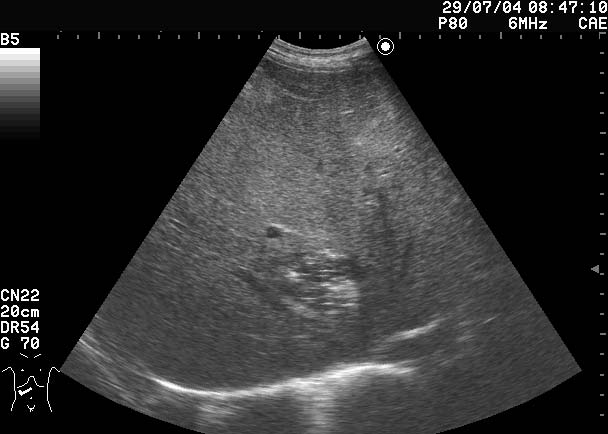

Все верно, абсцесс печени

Дренирован, динамика - см по числам в правом верхнем углу сонограмм